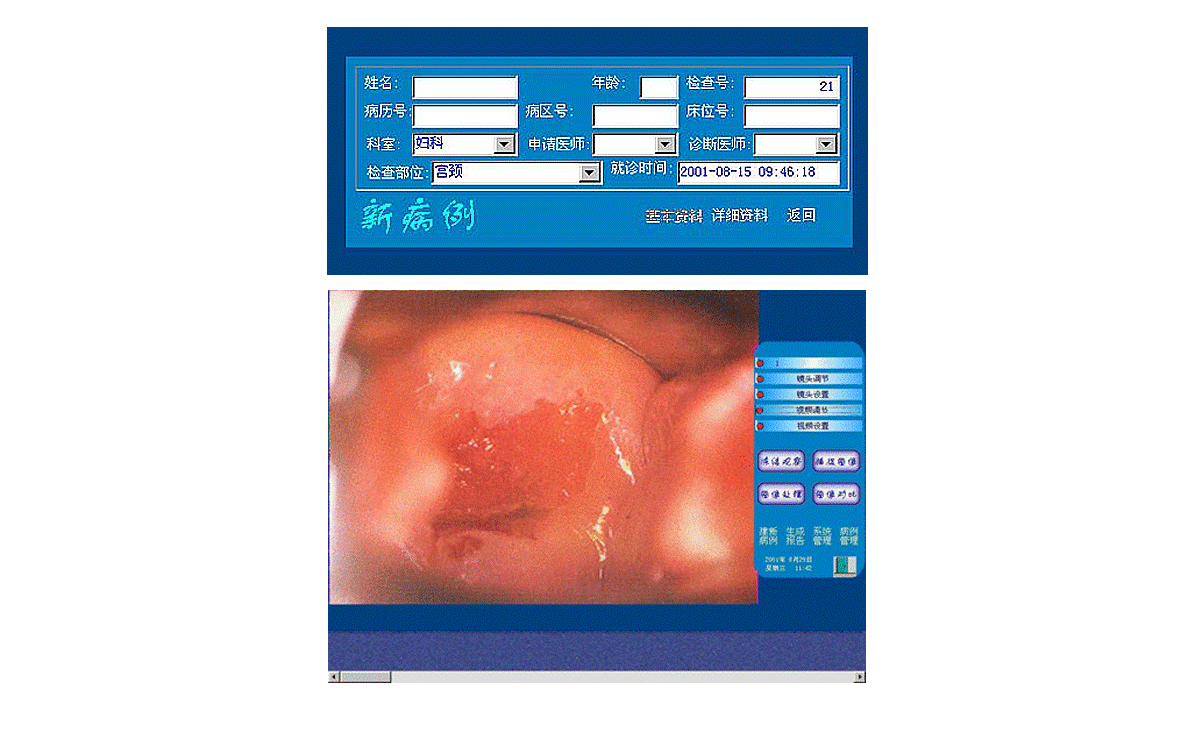

3、打開顯視器電源開關,開啟主機電源總開關,開啟陰道鏡系統,待系統進入正常窗口界面后,先創建新病例,通過觀察、采集、生成報告后,即可完成整個陰道鏡檢查與診斷操作。

2、用鼠標點擊主界面窗口中<建新病例>按鈕后輸入病人的一些資料,再點擊該窗口上的<返回>按鈕,系統進入圖像采集窗口界面,這時圖像采集窗口將顯示陰道鏡所觀察到的動態影像。